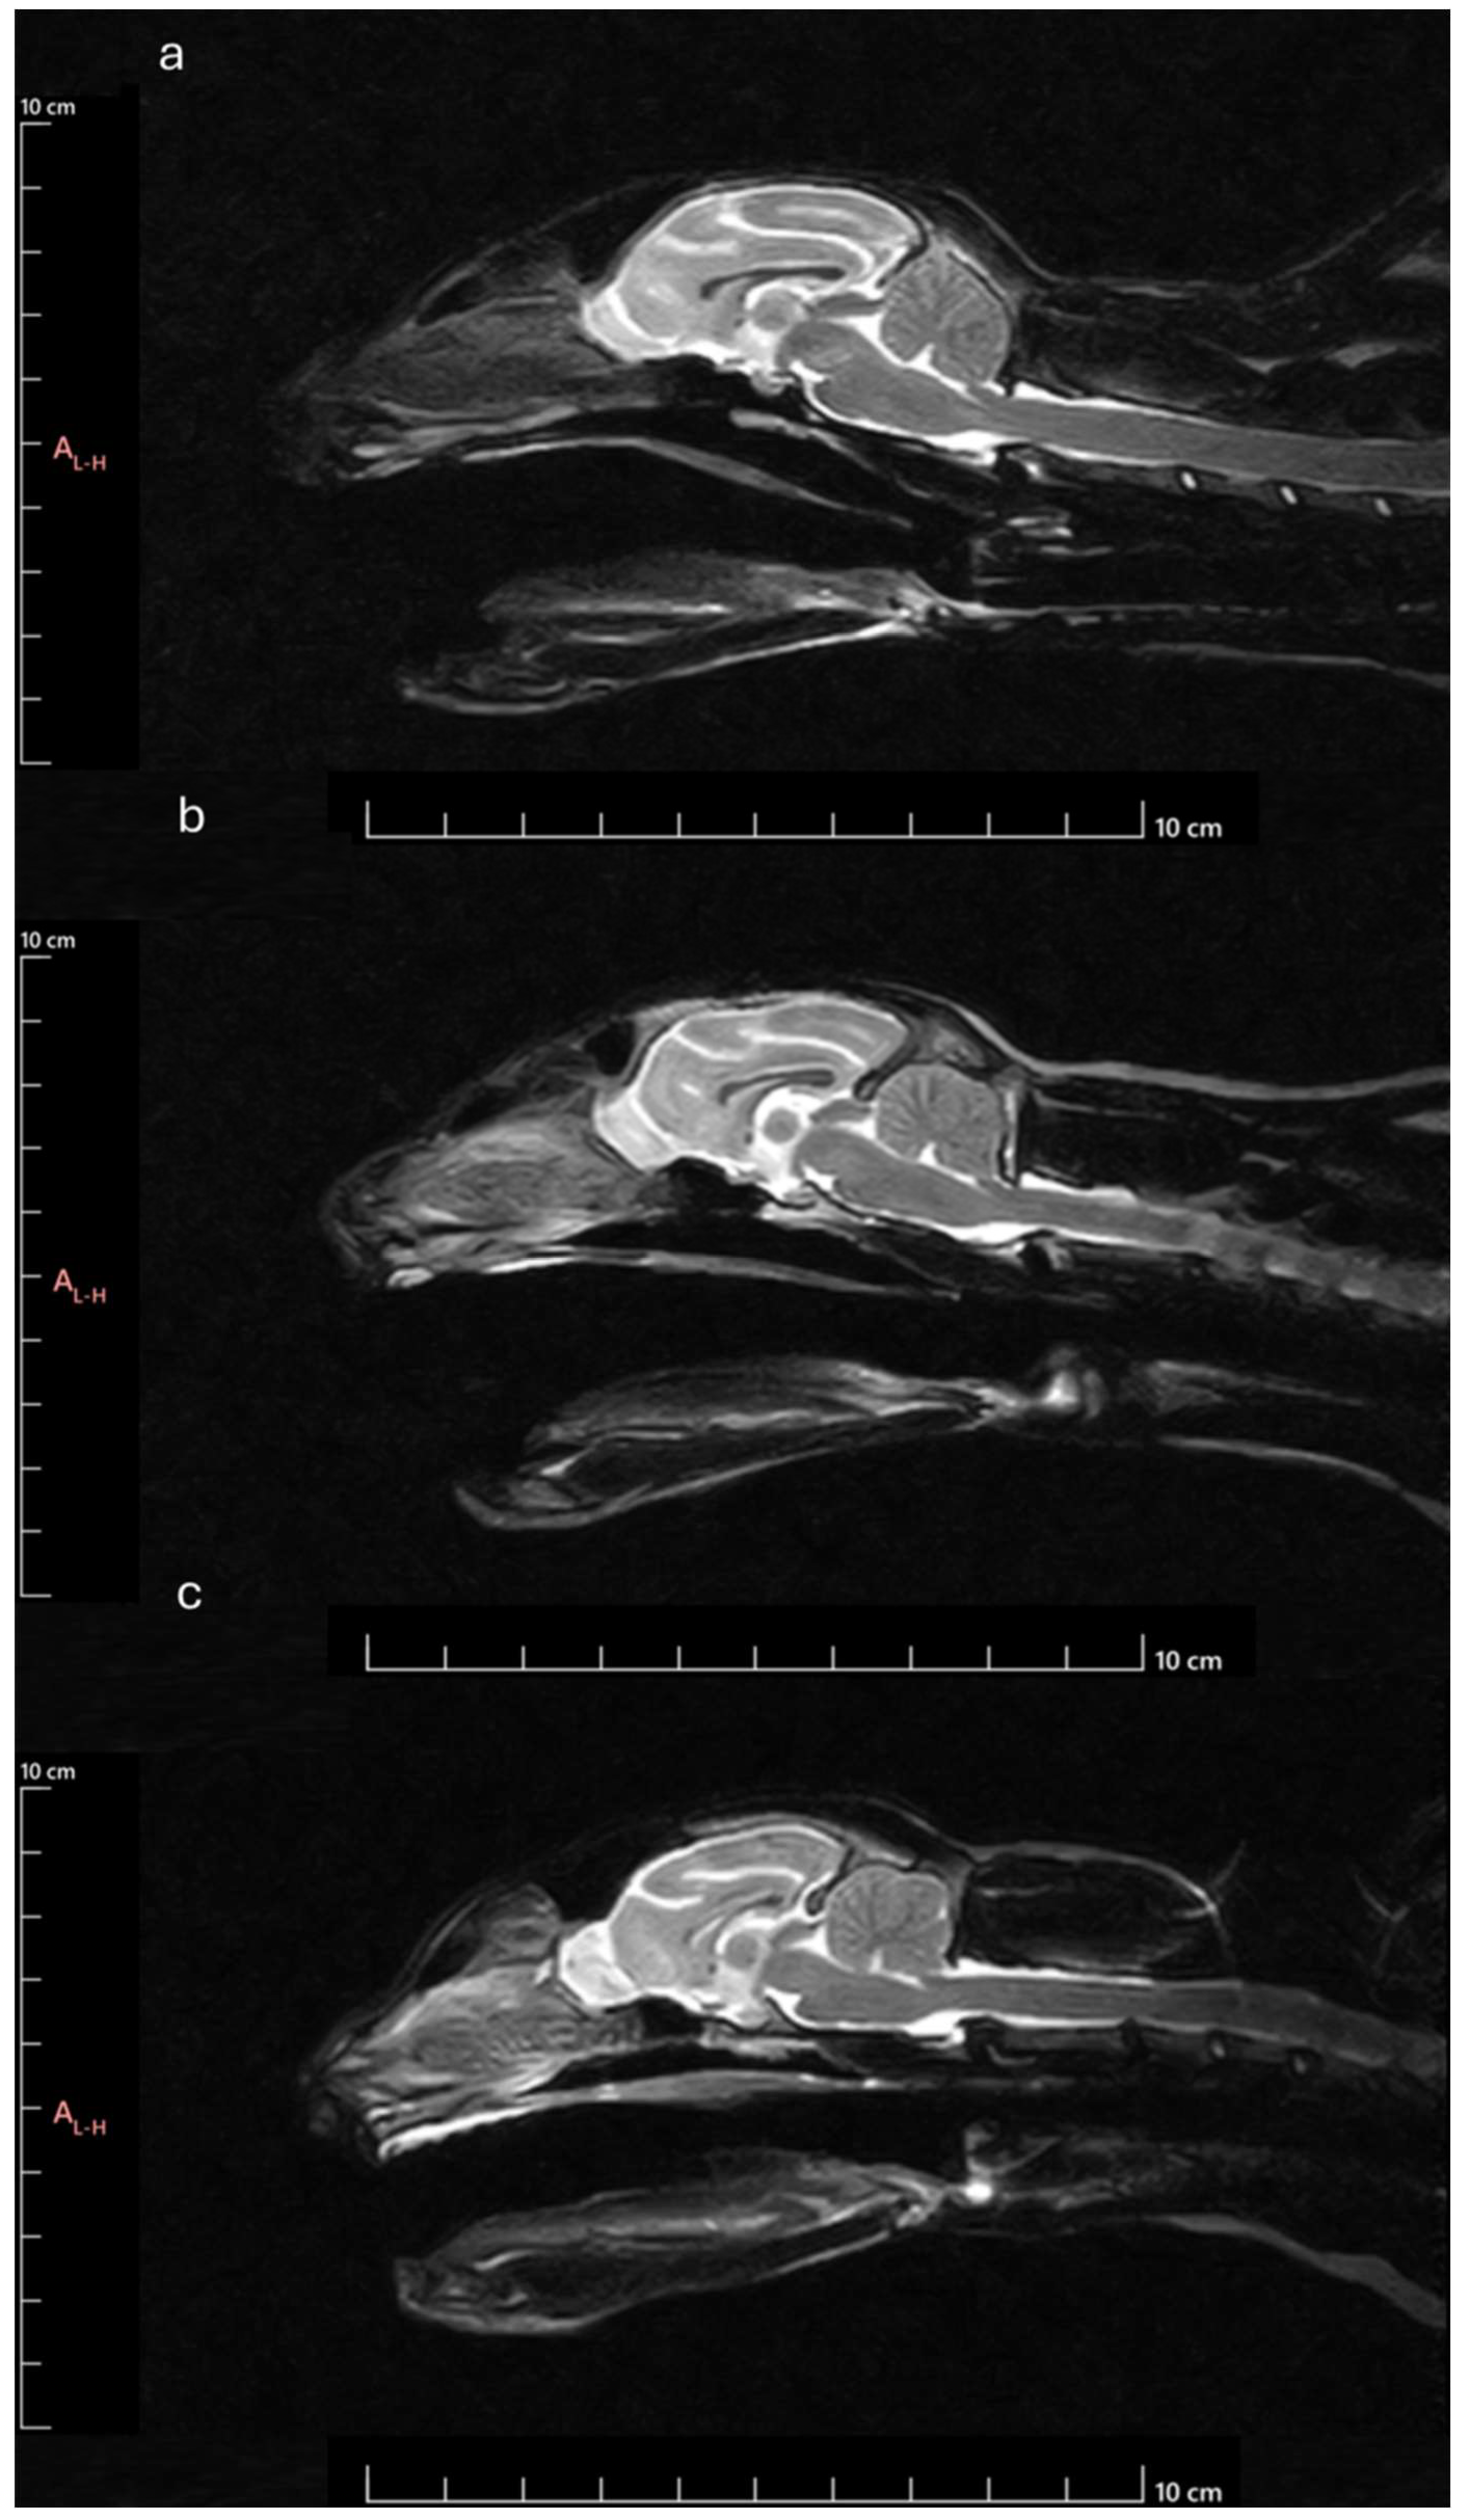

Figure 12. MRI Midsagittal T2-weighted images of animals with different head conformations: a) animal classified as brachycephalic – ventral orientated and compressed OB with smaller OBSA, smaller OBA and smaller OBO; b) Animal classified as mesocephalic - OB with intermediate orientation and OBSA, intermediate OBA and intermediate OBO; c) Animal classified as dolichocephalic – dorsally orientated and globose OB with larger OBSA, higher OBA and higher OBO.